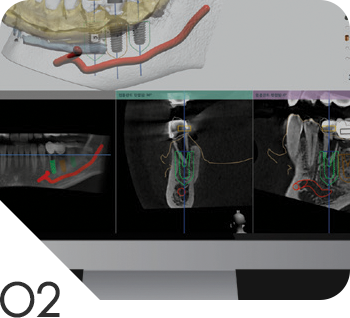

02

3D모의 시술로 식립

컴퓨터 가상 수술을 통해 최적의 임플란트 식립 위치 및 깊이를 미리 결정하고

원가이드를 제작, 구강에 장착하여 수술하기 때문에 육안으로 판단하는 일반 수술 대비 정확도가 매우 높고 안전합니다.